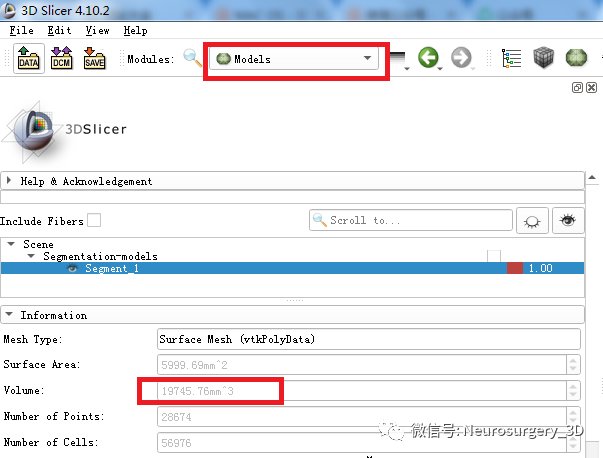

5、利用segmentations分割工具生成血肿Models模型

在Models血肿模型中可自动计算血肿体积19.74ml